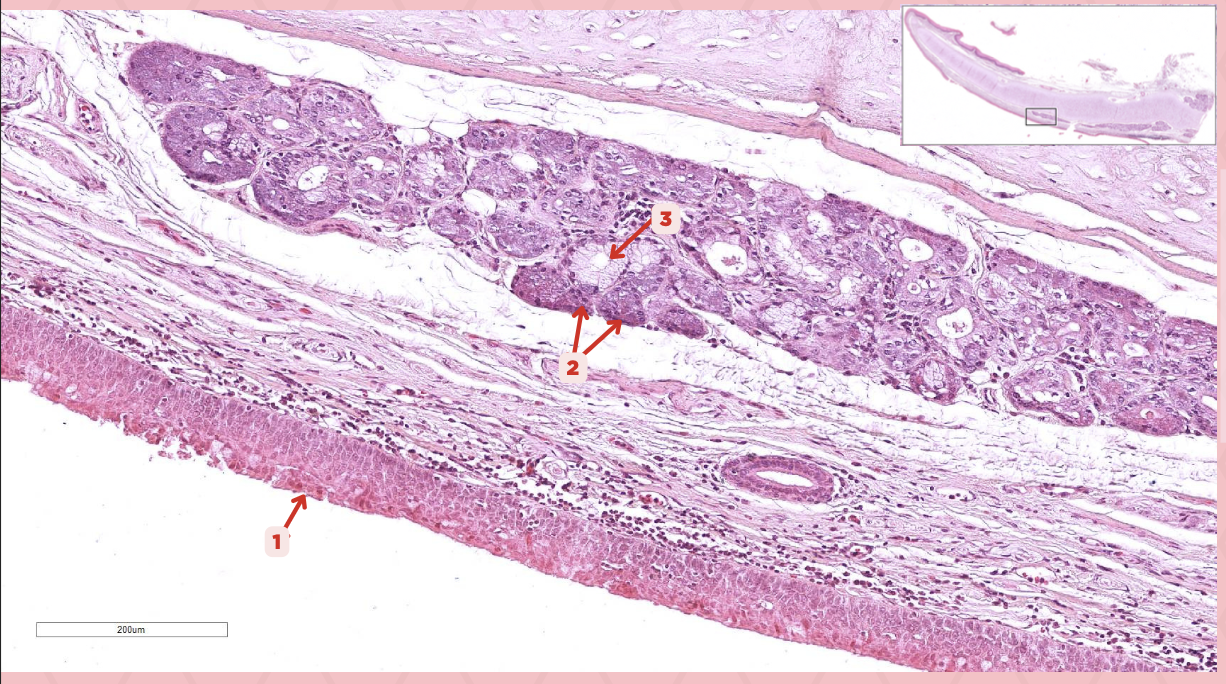

Epiglottic Elastic Cartilage

Identify the structure labeled as 1.

Serous Gland

What is the gland at #2?

Mucous Glands

What is the gland at #3?

Unpaired cartilage

What is the type of elastic cartilage at #1, paired, or unpaired?